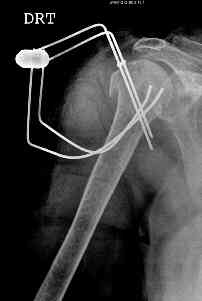

Re: Comminuted fracture proximal humerus

This fx need to be manipulated, reduced and fixed. We developed a minimally invasive ex fix with Ilizarov parts to fix it, we call it “Spider”, which can hold 4 fragments.

Attaching a case.